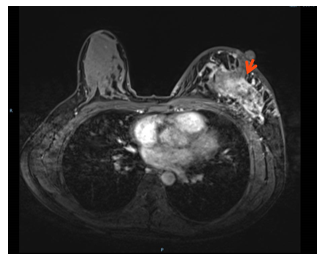

1.乳腺增强MRI:左侧乳腺多发肿块,形态不规则呈分叶状,边缘毛刺,内部呈不均匀混杂强化,病灶最大直径约7.2cm(靶病灶1)。(图1)

图1. 乳腺增强MRI

1.靶病灶1(乳腺原发病灶)评效:2周期部分缓解PR,4-6周期乳腺病灶呈非肿块样强化,无法测量病灶大小,8周期复查无强化,疗效达CR。(图7)

图7 靶病灶1(乳腺原发病灶)评效CR